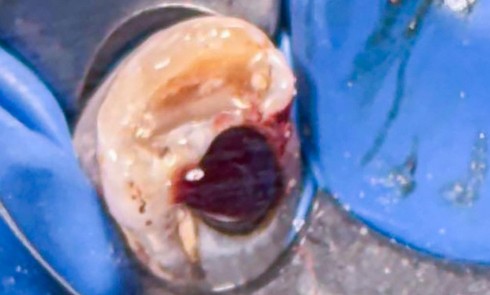

Très souvent, l’implantation peut être réalisée dans le même temps opératoire que l’extraction, avec des taux de réussite égaux à...Une lecture efficace au service des patients